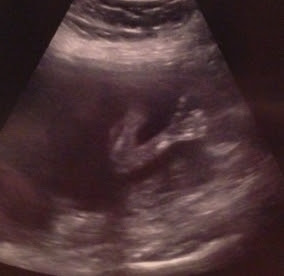

So we had our ultrasound this morning and found out that we are having a BOY!! We're thrilled because now we will have one of each. He was wriggling around the whole time and it was amazing to watch. He kept pulling his knees up and then straightening them out again, and bringing his hands up to his face. I think all this movement was due to the orange juice and sour patch kids that I ate for breakfast. My doctor appointment also went well. She told me that all the fluids around him look good and normal and that everything is normal sized. I have to go in for another ultrasound in a month because they couldn't get clear pictures of a couple things like his kidneys because of the way he was positioned. Marlana and I went shopping after work today and picked up multiple cute newborn outfits. It's so fun to finally be able to shop!

Ultrasound Picture #1 - Full Profile

Ultrasound Picture #2 - Thumbs Up! (This one makes me giggle)

Ultrasound Picture #3 - Spine, Bottom & Legs

Ultrasound Picture #4 - Legs & Feet

Ultrasound Picture #5 - Face